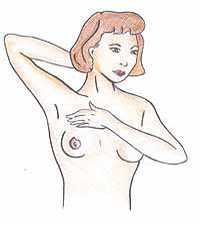

1. Εξέτασε το μαστό σου στο μπάνιο

1. Εξέτασε το μαστό σου στο μπάνιο

Με τα χέρια τεντωμένα ψηλάφισε όλη την επιφάνεια του μαστού.

Ψάξε για οτιδήποτε ασυνήθιστους όζους ή αύξηση του πάχους του μαστού.